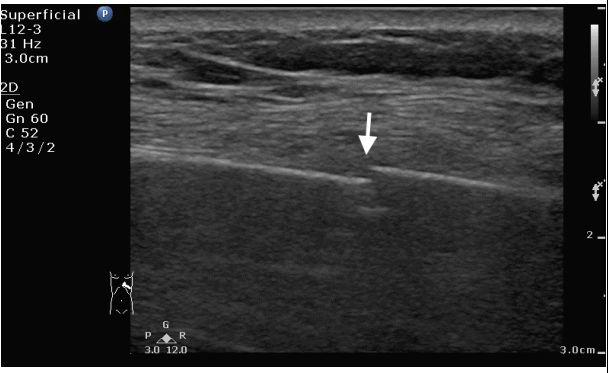

100. 65 歲女性,在浴室跌到撞到左胸前下側,胸部 X 光無明顯骨折,因持續 疼痛,以超音波進行左胸疼痛處掃掃描,請問白色箭頭所指之病灶 最有可能 為下列那一個診斷? (A) Muscular hematoma 。 (B) Pneumopericardium 。 (C) Pneumothorax 。 (D) Rib fracture 。 (E)Subcutaneous emphysema 。